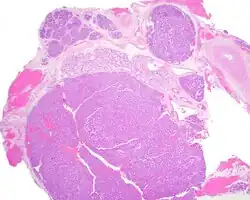

Canalicular adenoma is a type of growth that occurs in human salivary glands. It is a benign growth which occurs in the epithelial cells, and is typically arranged in columns of cells that form interconnecting cords. Canalicular adenoma is a very rare benign neoplasm; it constitutes about 1% of all salivary gland tumors and about 4% of all benign salivary gland tumors.[1][2]

Canalicular adenoma is most common in patients age 70 to 80, with females affected about four times as often as males. Most growths present in the upper lip; some also occur in the a few present in palate or buccal (cheek) tissue as a slowly enlarging mass.[3] The growths will often arise in multiple places at the same time or develop multiple nodes, despite not being clinically invasive or malignant.[1][4]

Canalicular adenoma growths are usually small at the time they are noticed, with an average size of about 1.6 cm.[1] Their histologic appearance is very distinct, with a channel-like pattern between cords and ribbons; the pattern has been described as resembling a "string of pearls."